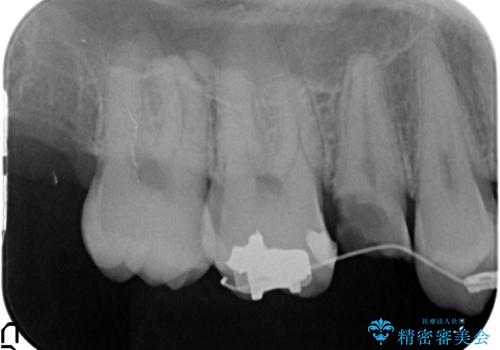

放置した虫歯 歯ぐきの中まで虫歯でも、しっかり健康的な部分を引っ張り出して、きちんと処置します。

- 放置した虫歯の治療で来院。

歯茎の中まで虫歯になっており、そのまま完璧に治療をすることは不可能でした。

歯の健康な部分を矯正治療で引っ張り出してから、虫歯治療を行なっています。

開始前